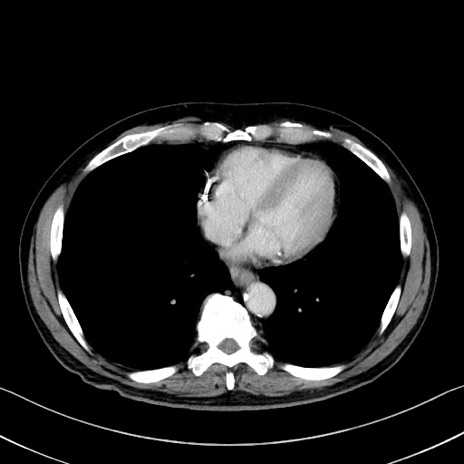

症例35(横断像)

【症例】70歳代 男性

【主訴】腹部膨満、嘔吐

【現病歴】昨日より腹部膨満感出現。本日増悪し、仙痛出現。嘔吐あり、受診。

【既往歴】糖尿病、胆摘後

【身体所見】BP 149/80mmHg、HR 74/min、BT 35.9℃、腹部:膨満、軟、圧痛なし。腸雑音減弱あり。上腹部正中切開瘢痕あり。

【データ】WBC 13500、CRP 1.72